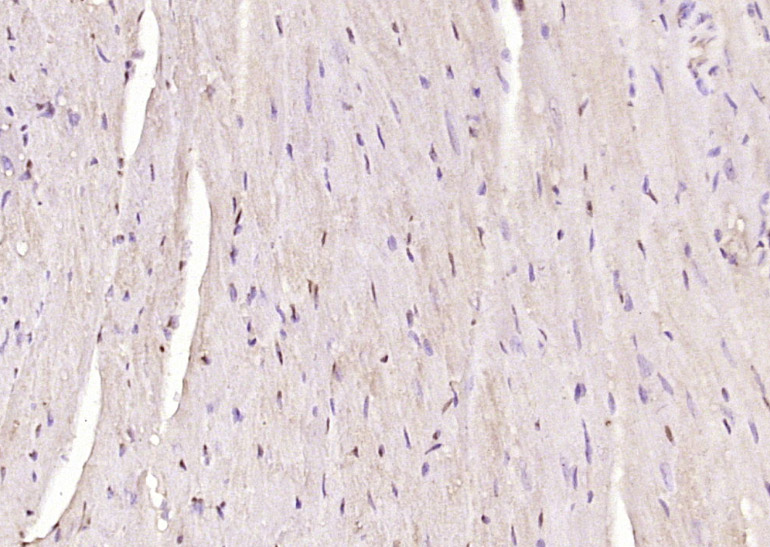

Paraformaldehyde-fixed, paraffin embedded (mouse heart tissue); Antigen retrieval by boiling in sodium citrate buffer (pH6.0) for 15min; Block endogenous peroxidase by 3% hydrogen peroxide for 20 minutes; Blocking buffer (normal goat serum) at 37°C for 30min; Antibody incubation with (PHD3) Polyclonal Antibody, Unconjugated (bs-0532R) at 1:400 overnight at 4°C, followed by operating according to SP Kit(Rabbit) (sp-0023) instructionsand DAB staining.